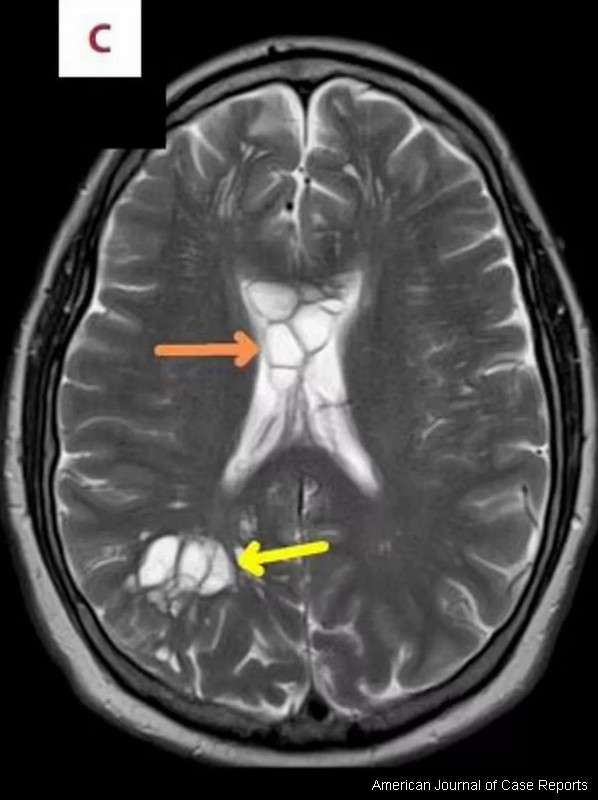

a stručnjaci su potvrdili da ih je izazvala svinjska trakavica koja je položila jaja u njegov mozak.!

Stanje, poznato kao „parazitska infekcija neurocisticerkoza“, nastaje kada se delovi tela upale kao rezultat svinjske trakavice. Lekari smatraju da je parazit ušao u njegovo telo nakon što je pojeo nedovoljno kuvanu hranu, a zatim je prešao iz creva u mozak kroz krvotok.

Slučaj je objavljen u American Journal of Case Reports. Lekari su napisali: „Doživotna preferencija našeg pacijenta za mekom slaninom možda je dovela do slučajeva konzumiranja nedovoljno kuvane slanine piše dailystar